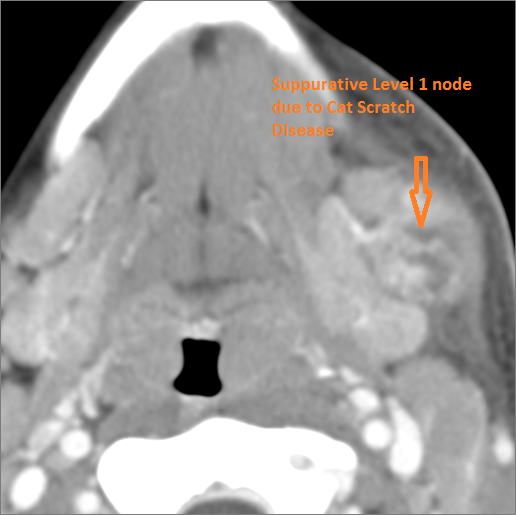

30-year old male with left facial swelling and tenderness mainly in the submandibular space. Primary clinical suspicion was an odontogenic infection.Exam

CT: Contrast- enhanced CT of the maxillofacial region and neck and related anatomy with images obtained in the balanced or venous vascular phase to ensure optimal visualization of both arterial and venous structures as well as possible reactive changes around infected collections. 0.5-3.0 mm thick sections were obtained in the axial plane and reformatted 3D and/or in the coronal and sagittal planes and viewed inter actively in 3 dimensions at the computer work station.